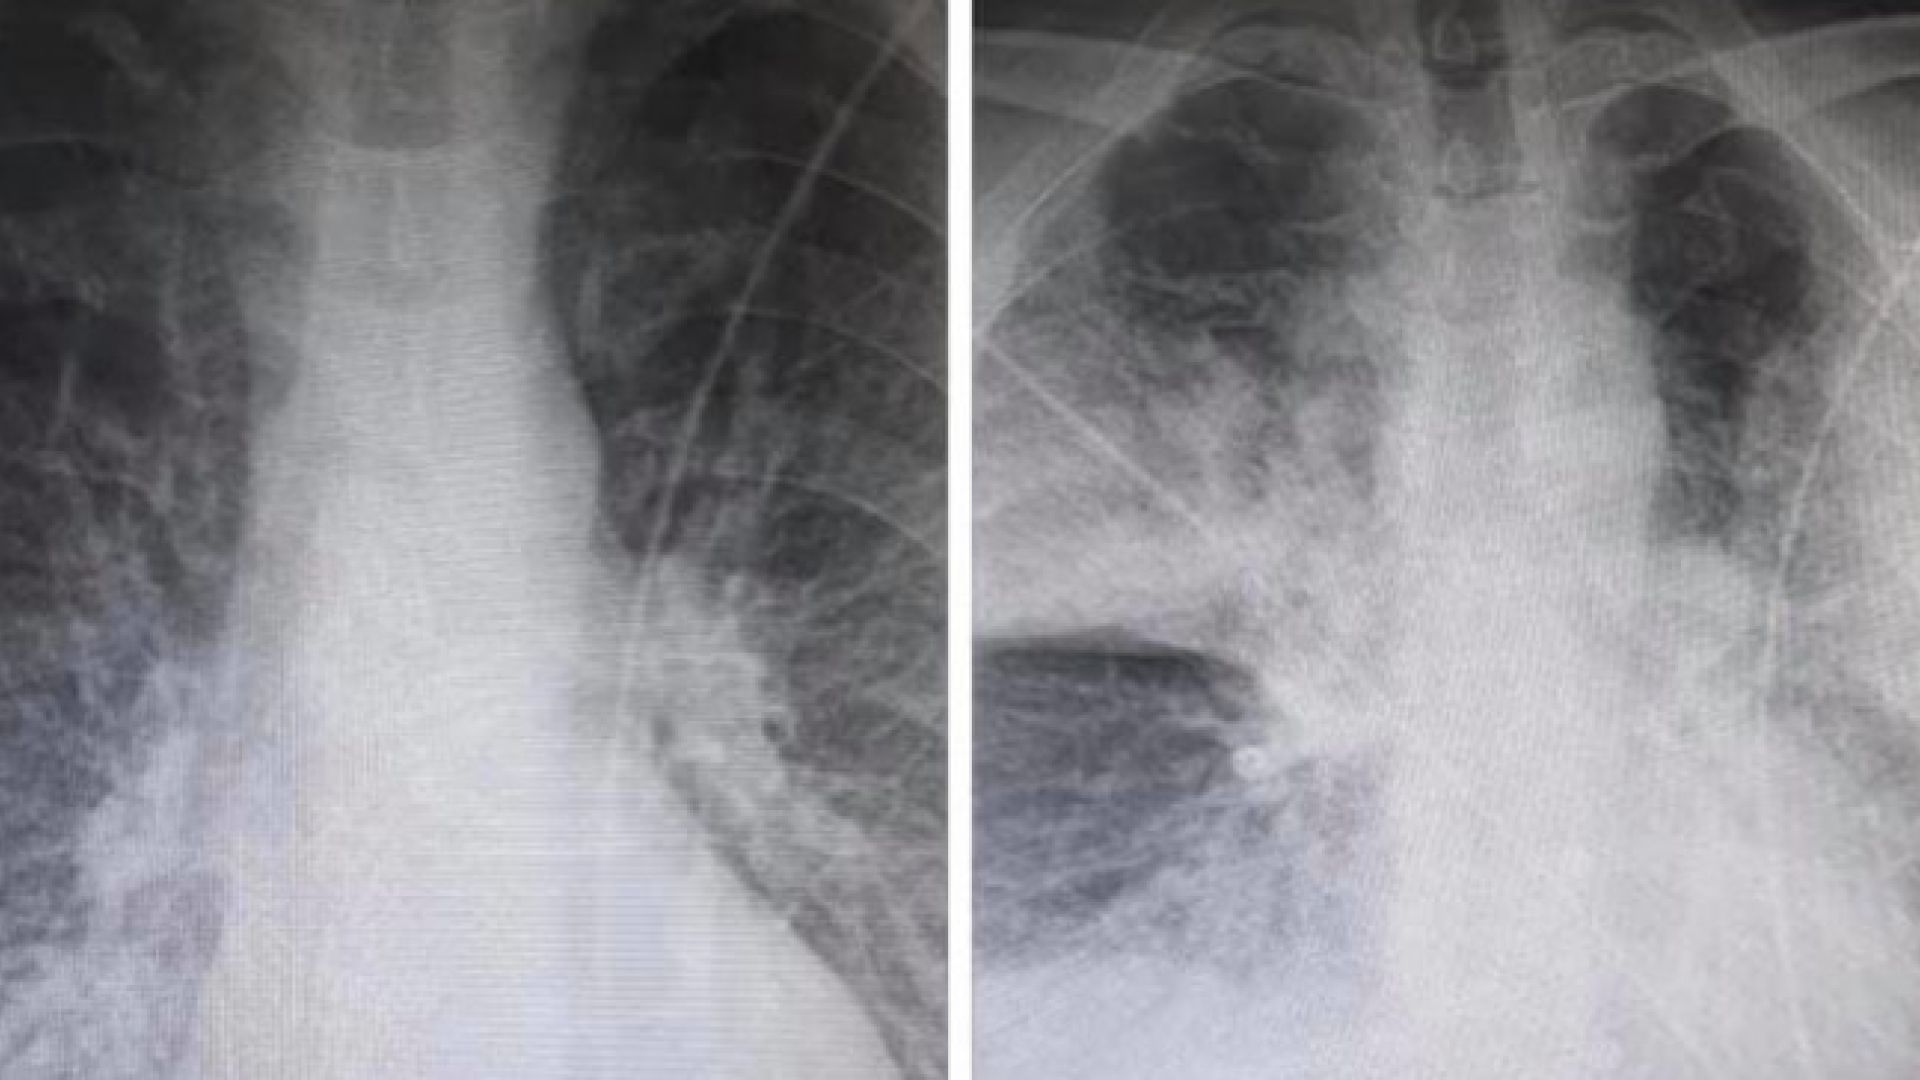

Σοκ προκαλούν οι δύο ακτινογραφίες που ανάρτησε στο Facebook ακτινολόγος από το ΚΑΤ, καθώς αποδεικνύουν την επίδραση που έχει ο κορωνοϊός στους πνεύμονες των ασθενών.

Όπως περιγράφει ο ακτινολόγος του ΚΑΤ Μάνος Καρράς οι δύο ακτινογραφίες ανήκουν σε έναν 38χρονο, ο οποίος είναι καπνιστής και διαβητικός. Σύμφωνα με τον ίδιο, οι ακτινογραφίες έχουν καταγραφεί με 7,5 ώρες διαφορά.

Η πρώτη είναι από την εισαγωγή στις 12 το μεσημέρι με 98% κορεσμό οξυγόνου και η δεύτερη, η επαναληπτική, πραγματοποιήθηκε στις 19:30 με τον ασθενή να είναι πλέον με μάσκα οξυγόνου.

Όπως εξηγεί σε σχόλιο στην ανάρτησή του ο κ. Καρράς, τα «σύννεφα» στη δεύτερη ακτινογραφία συνήθως σημαίνουν υγρό οίδημα φλεγμονή και «είναι κομμάτι του πνεύμονα που “δεν αναπνέει”».